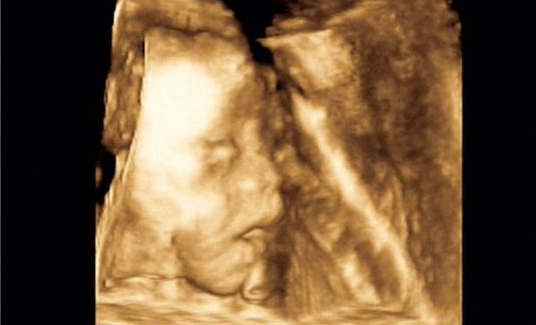

医院概况 >> 合肥安琪儿特色服务 >> 宝宝4D写真

宝宝4D写真